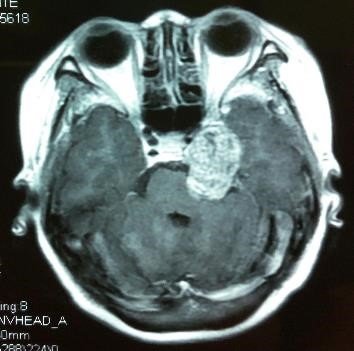

巨大中后颅窝沟通哑铃型三叉神经鞘瘤的手术治

354x351 - 23KB - JPEG